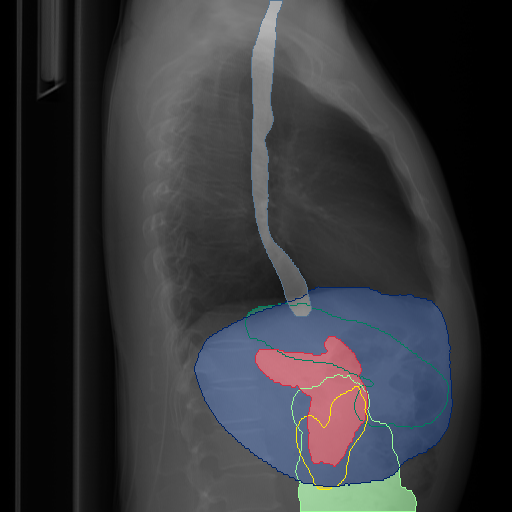

We show qualitative results for frontal projections in Fig. 2. We show a subset of classes belonging to the supercategories lungs, vascular systems, bones, and abdomen/digestive system. The predictions show minor deviations at the boundaries of the individual classes of the respiratory and vasculature system, while some inaccuracies become visible in the abdominal area. The qualitative results for the lateral projections are displayed in Fig. 2. Akin to the frontal view, the predictions show smoother borders but align with the ground truth. Apart from this, the segmentations provide matching insights on the thoracic anatomy with a slight deviation from the ground truth for both frontal and lateral views.

Fig. 2 shows quantitative segmentation results for frontal (top row) and lateral (bottom row) views. We display the class performances in the form of IoU (left), DICE (center), and Hausdorff distance (right) for each sample as a scatter plot with the mean performance for the classes shown by a line plot. Generally, we see performances for standard spinal classes, such as the thoracic vertebrae with average IoU-scores above 80%, while the average performance of rare vertebrae of the dataset belonging to the cervical and lumbar spine can drop down to 40%. In the frontal view, there exists more variance in thoracic vertebrae segmentation performance compared to the lateral view. Bone structures such as the sternum, clavicles, and scapula achieve IoUs in the mean from 85% to 95%. For ribs, we can see a noticeable performance drop for the anterior parts of the lower ribs independent of the side. The lower anterior ribs typically do not contain a large area, making them difficult to segment. This behavior is mirrored in the lateral view across the metrics. Abdominal classes can vary in segmentation quality as they occur in a nearly homogenous region. For example, while the liver or stomach are typically well-segmented, the duodenum and kidneys are more complex. Heart and Lung related classes show near-perfect segmentations with scores above 90% IoU. Breast tissue segmentation in comparison only achieves a mean of 70% mIoU. It can be noted that classes in the lateral view tend to have slightly better scores than their frontal counterparts.